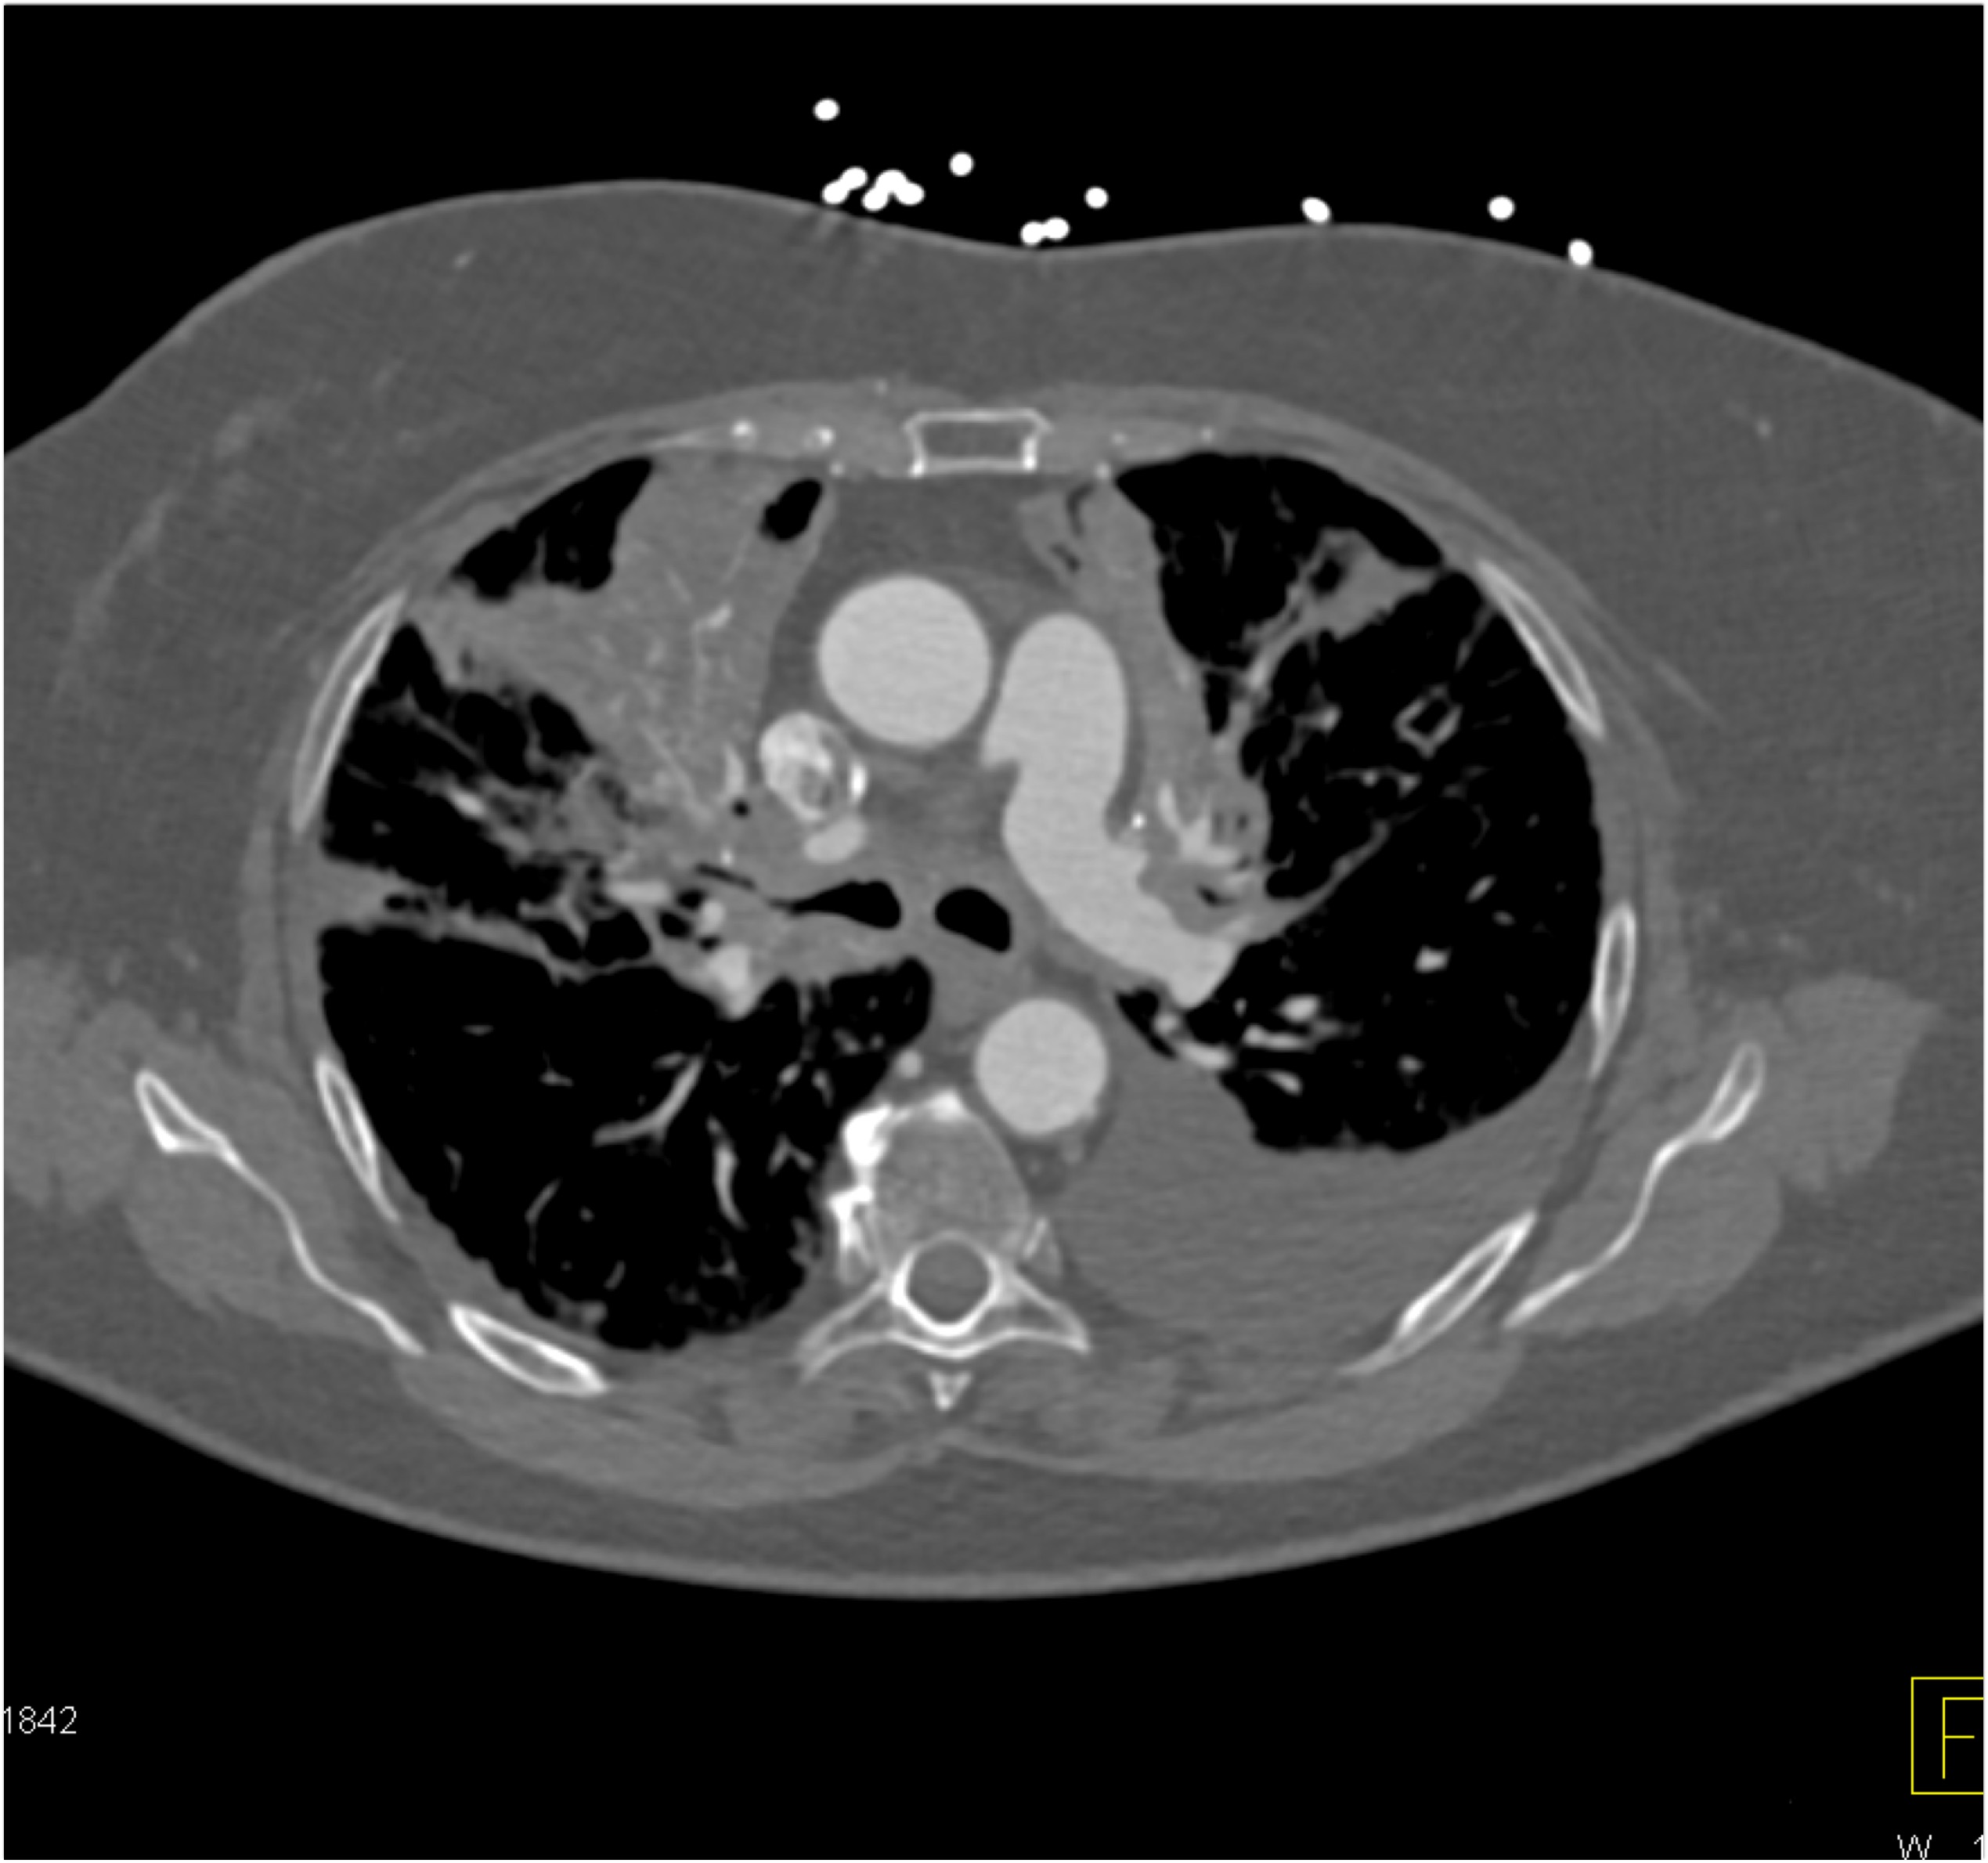

4) The least likely diagnosis in this case is?

fibrosing mediastinitis

sarcoidosis

lymphoma

COVID pneumonia